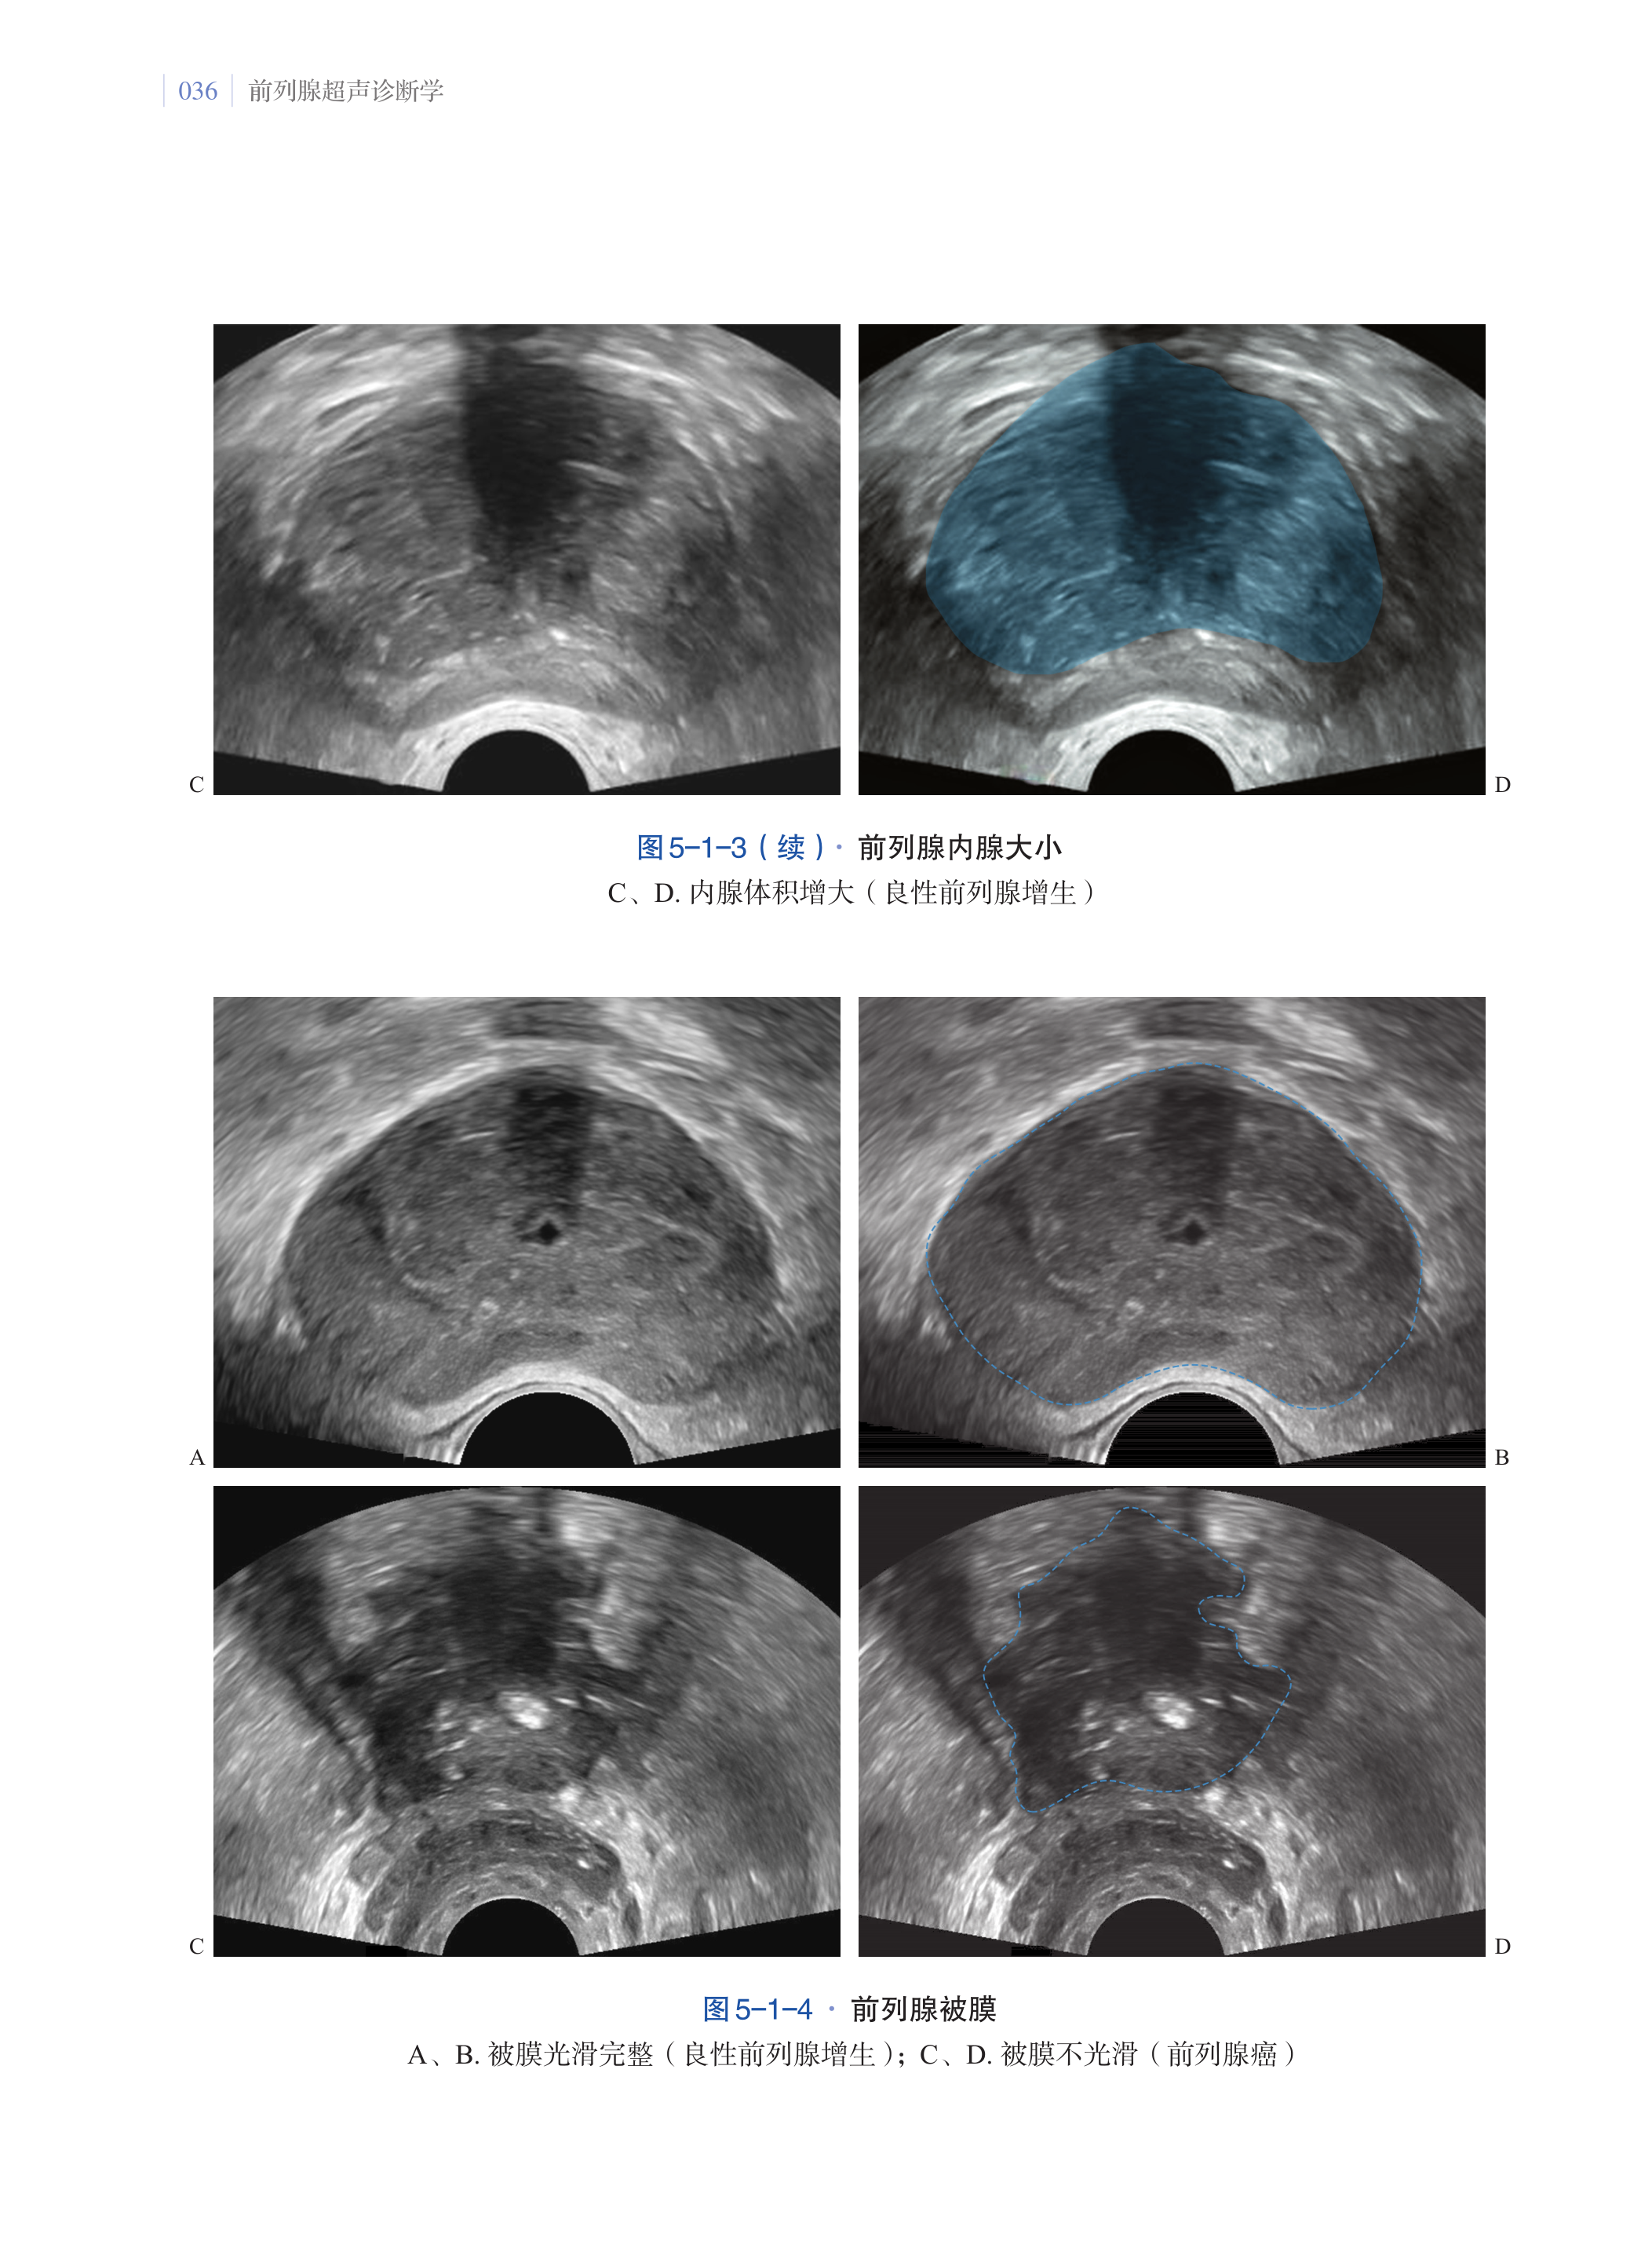

第五章·前列腺超声图像解读及伪像 033

第一节·前列腺超声图像解读 033